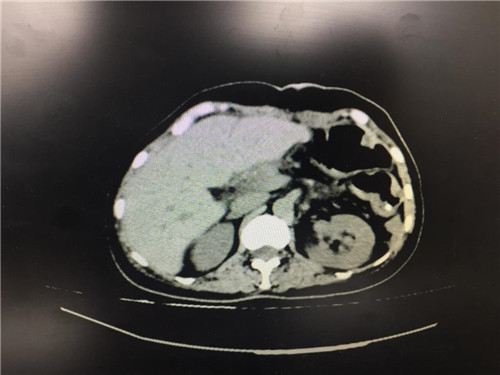

患者病情复杂,在潘承恩教授和全科医生的讨论下,结合检验及检查结果,术前胰腺颈体部肿瘤诊断明确,科室积极制定手术方案,详细向家属探明病情并取得合作。2月21日,由普外科史和平主任、梁鹏锋医师主刀,在王谦、李垚磊医师配合下,成功对该患者实施了剖腹探查、全胰腺切除、脾脏切除术。手术中发现,患者胰腺颈体部可触及一大小约4cm包块,胰头部质软,胰腺体尾部质硬,遂决定行胰腺颈体尾部切除及脾脏切除术。在胰腺近侧断端切取部分胰腺组织送术中快速冰冻,提示查见异型增生的胰腺腺泡样组织,联系病理科考虑癌细胞残留,术中向家属谈明病情并取得同意,遂行胰十二指肠切除术,手术顺利,术后生命体征平稳,并于术后第四日进行了复查CT结果良好。

术后,医护人员严密观察生命体征变化,并在内分泌科协助下,带胰岛素泵调整血糖并监测数值变化,在普外科医护人员的精心照料下,进行ERAS快速康复,患者恢复良好,疗效满意,3月7日已康复出院。